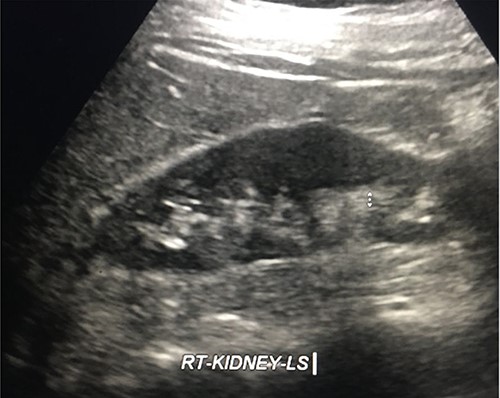

Three months later, the Urology department performed a retrograde ureteric stent exchange. Five months later, IR removed the ureteric stent via a retrograde approach. Retrograde ureterogram showed a fully healed, intact ureter. The ureteric stent was therefore not replaced. Three months later, follow-up ultrasound (US) showed no evidence of the obstruction (Fig. 10).